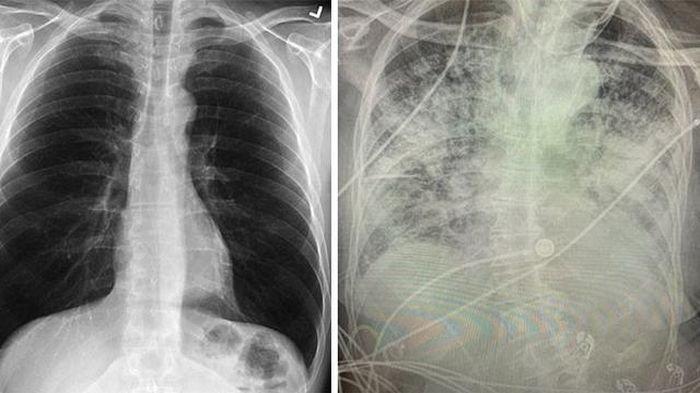

:quality(30):format(webp):focal(0.5x0.5:0.5x0.5)/prohaba/foto/bank/originals/Ilustrasi-Tampilan-paru-paru-sehat-kiri-dan-post-covid-19.jpg)